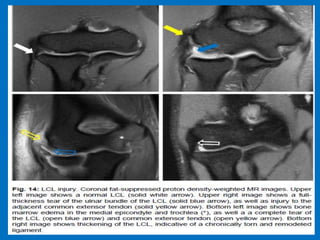

Complete tear of the LUCL.

Ulnar collateral ligament(UCL) injury refers to a sprain, partial tear or complete tear of the ligament that traverses the inside (or medial side) of the elbow. The UCL is the primary stabilizer of the elbow and plays an important role in throwing and hitting sports, such as baseball, football and tennis. Additional findings: Strain or rupture of the common flexor tendon, ulnar neuropathy, ulnar traction spurring or heterotopic ossification of the soft tissues

and medial flexorinsertion pronator tear.